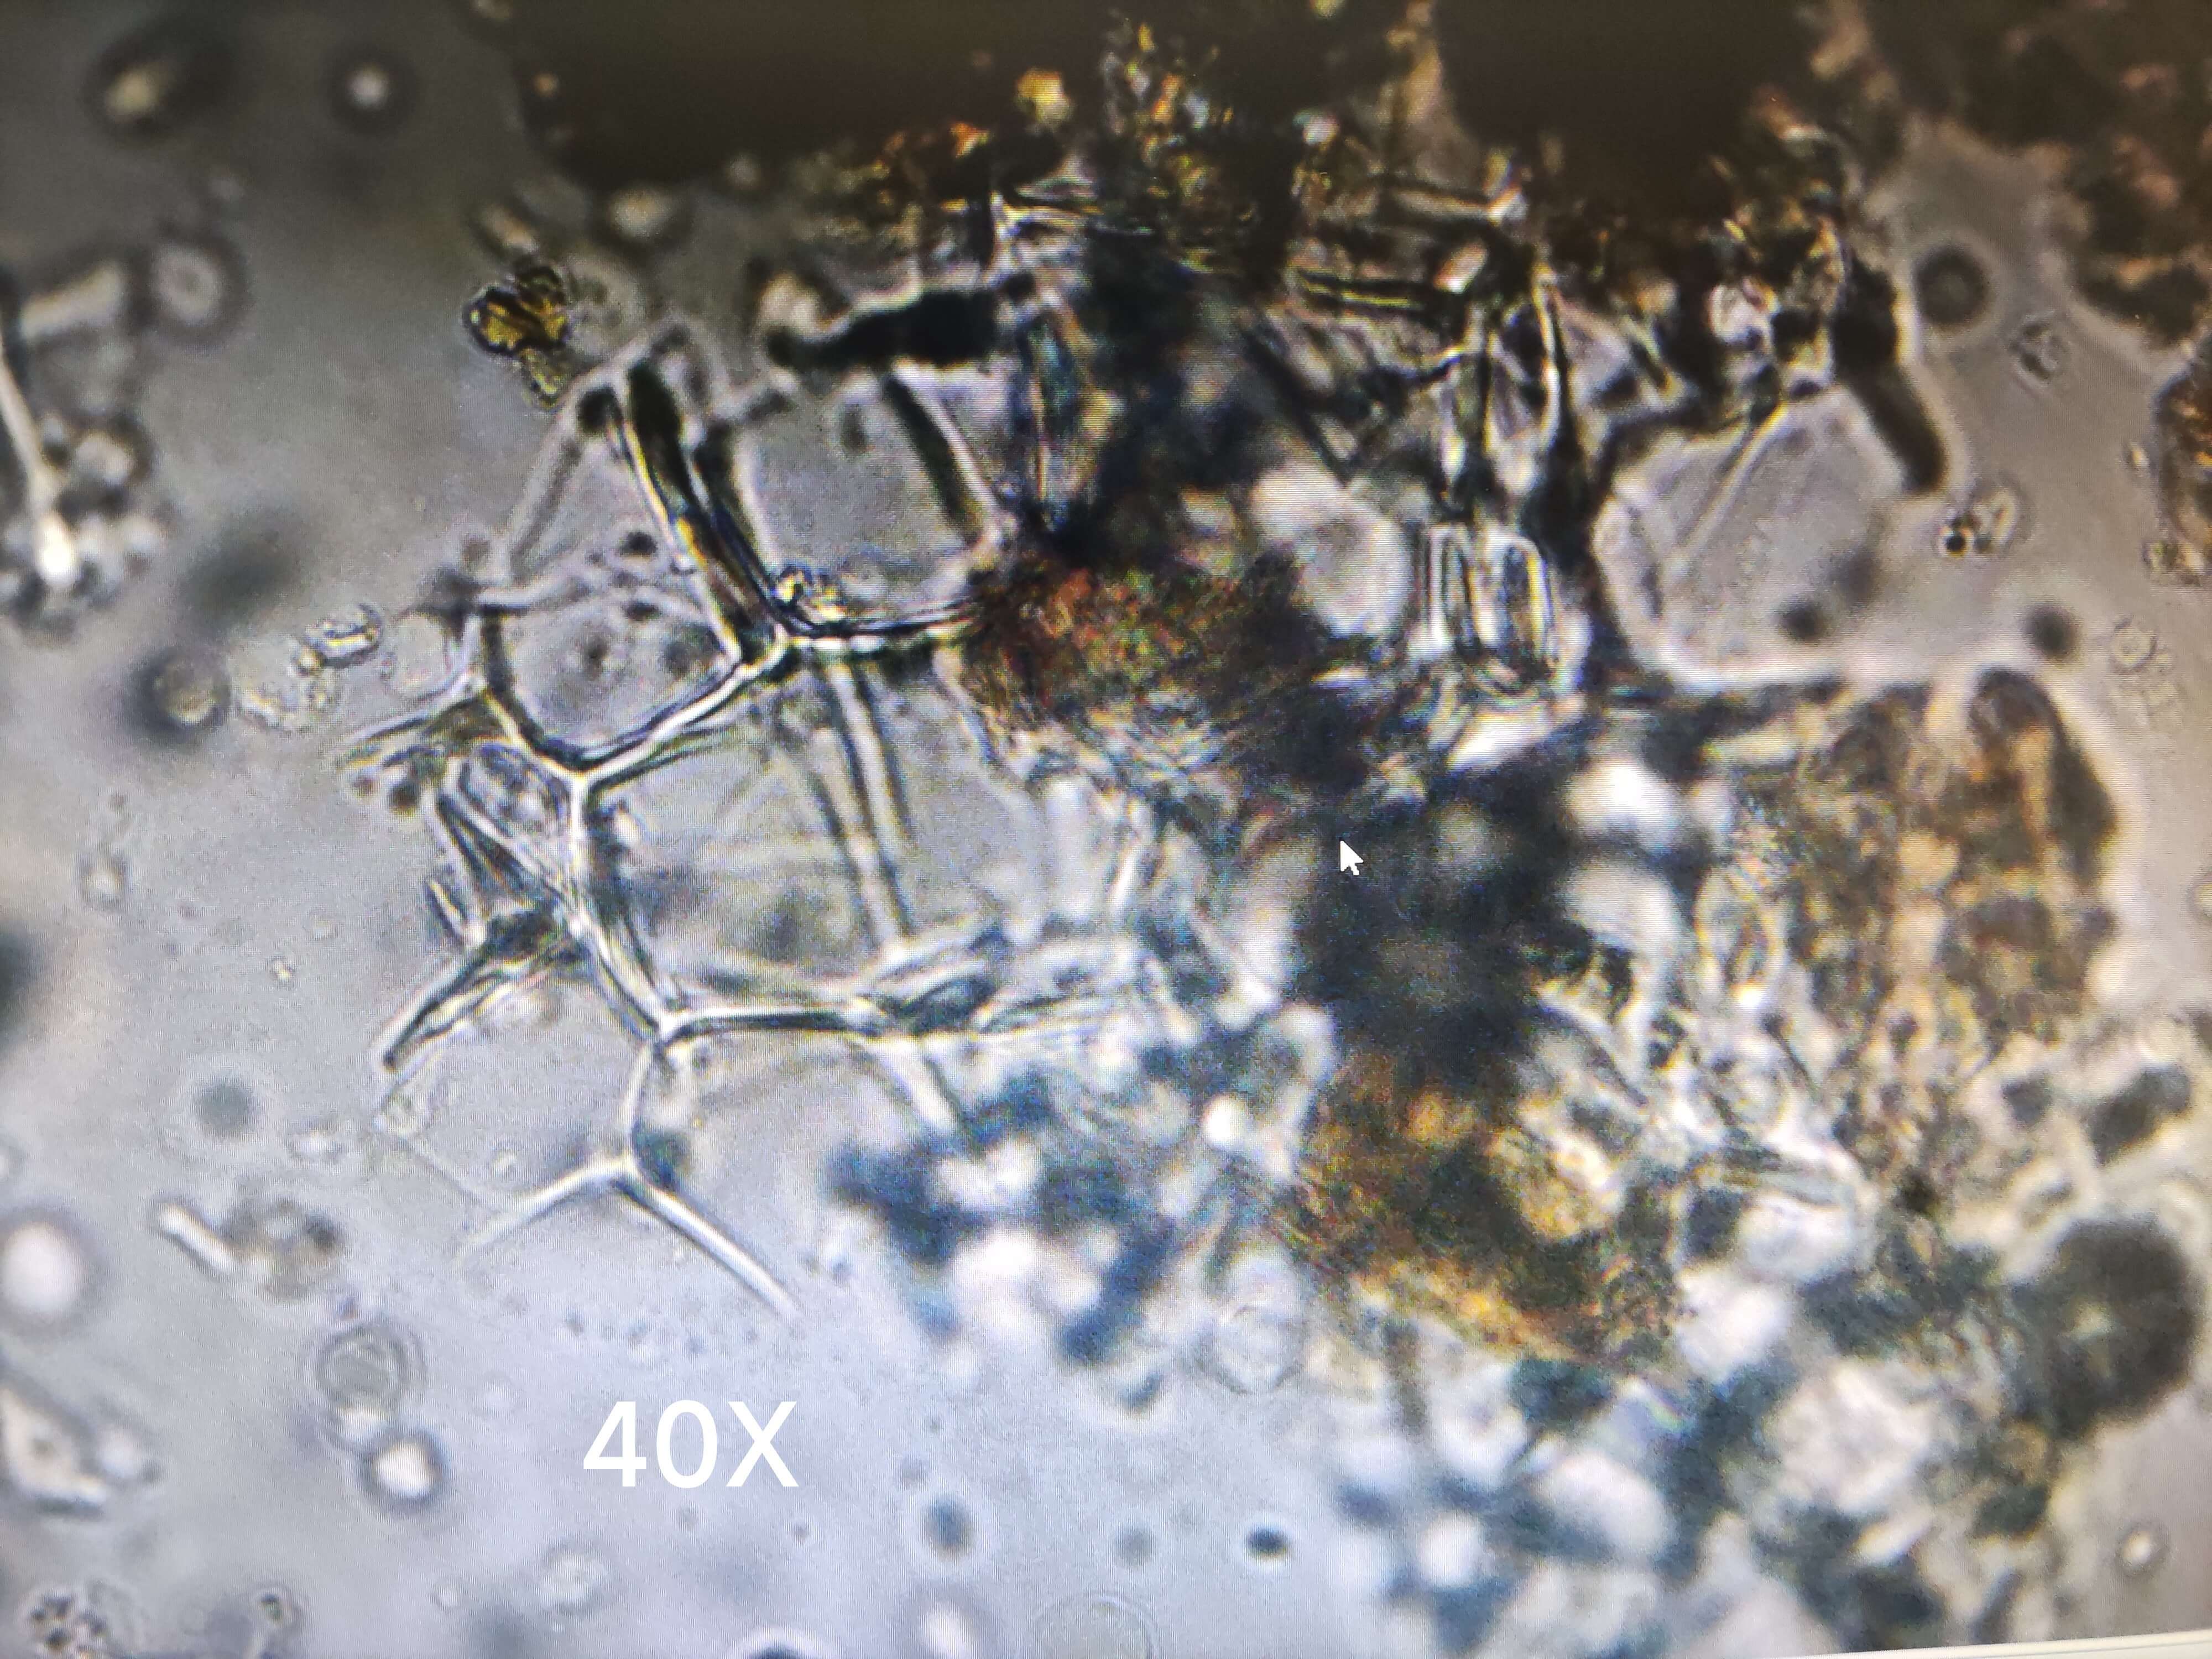

石膏

| 石膏 |

|---|

| 【参考文献】 《中药显微鉴定图典》(赵中振主编) |

| 【显微鉴别】 本品粉末为透明块状物,显微镜下观察,多呈薄片状、纤维状或类方形,表面光滑,断裂处呈层片状;偏光显微镜下呈亮白色至亮黄白色,以及至紫色。 |

| 【显微重点】 长柱状、薄片状、纤维状或类方形块状物 ,断裂处呈层片状。 |

| 【图谱来源】 《中药成方制剂显微图典》 |